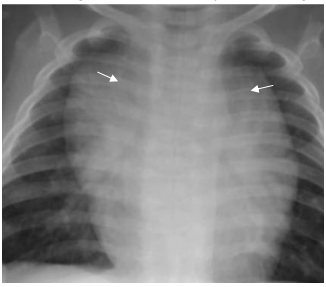

Observe a radiografia de tórax de uma criança de 4 meses a seguir:

Em relação à imagem, é correto afirmar que